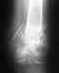

Несращение большеберцовой кости

В январе 2013 г упал с высоты на производстве. В январе-феврале выполнен остеосинтез бедра и обеих голеней.

В настоящий момент хожу с полной опорой на ноги, боли после длительной физической нагрузки. На контрольной Р-грамме несращение голени слева. Предлагают две операции - первая удаление штифта и шурупов, поставить пластину с донорской костью из таза. Вторая - удалить нижние винты. Но я беспокоюсь, что штифт пробъёт кость. Что посоветуете.